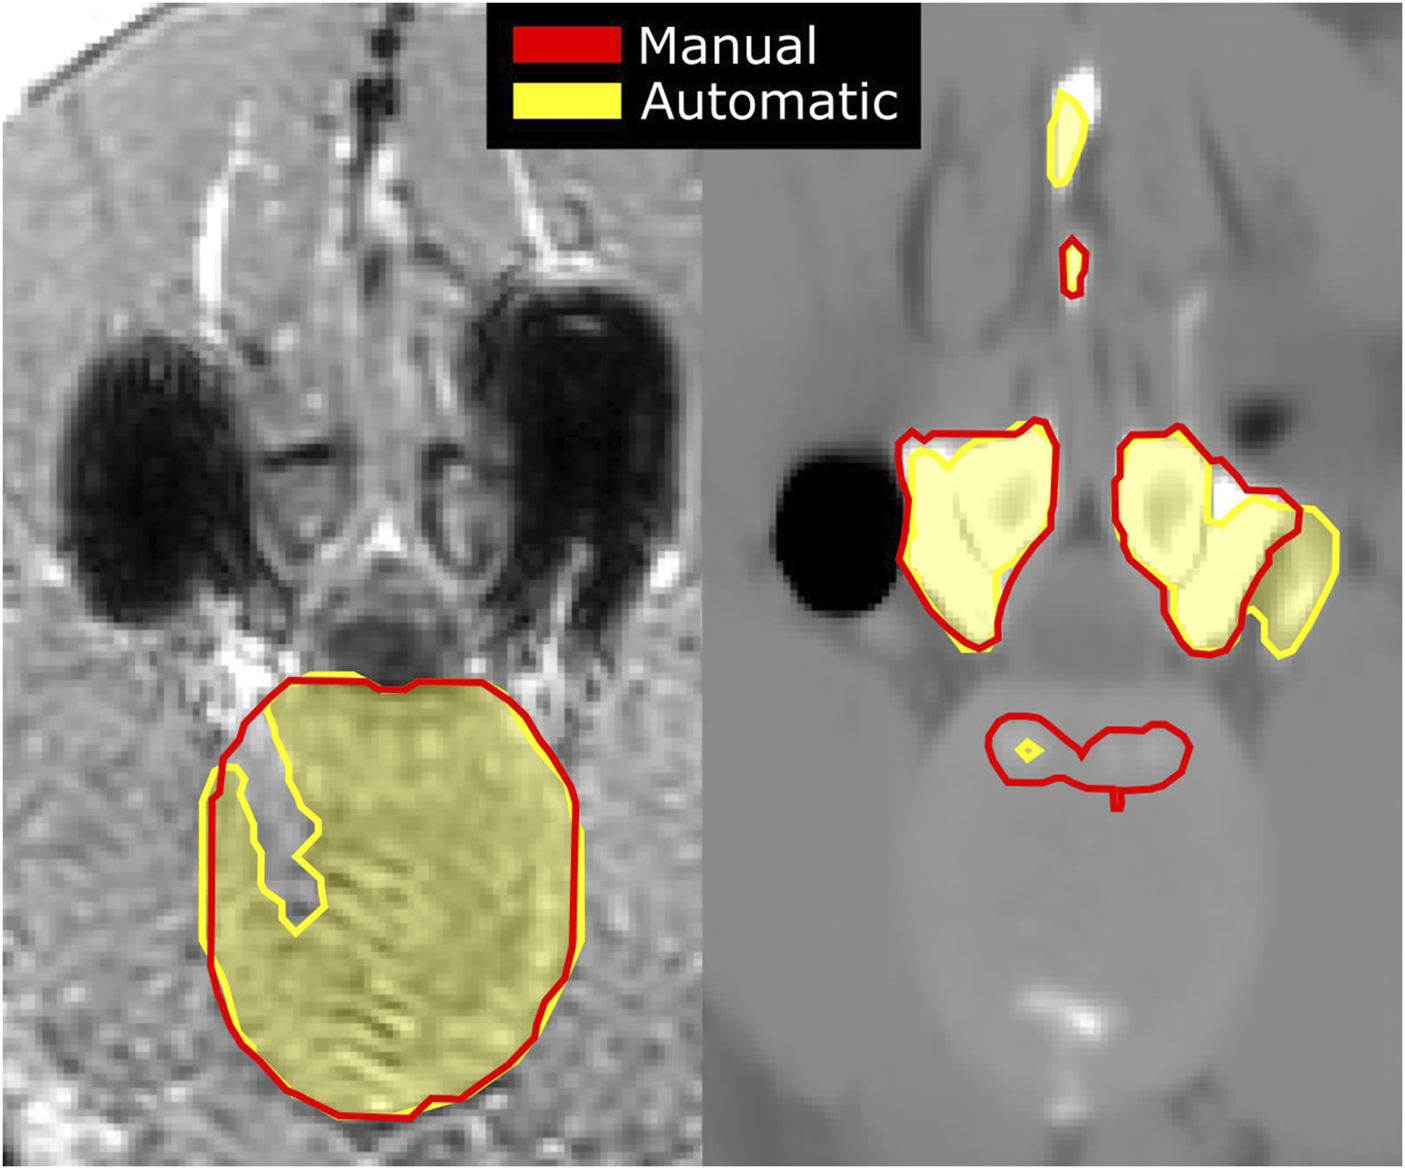

FIGURE 5

Artifacts originating from the spine implant on an acquired in-phase MR image (left), shown as dark signal voids, with manual (red) and automatic (shaded yellow) segmentations of the IVD; and an sCT image (right) of the same slice with artifacts originating from the signal voids leading to inaccurate segmentations of the vertebrae.

For the scoliotic spine, overall dice-scores of 0.93 (0.91–0.95) and 0.96 (0.95–0.97) were reached for the IVDs and the vertebrae, respectively (Figure 4). The largest differences between the segmentations of the vertebrae can be seen where the transverse processes reach outside the field of view. At these points the automatic segmentations do not consistently predict the bone to reach to the edge of the field of view, leading to under-segmentation. For the volunteer with implants, the achieved dice-score was 0.95 for all IVDs, excluding the L4-L5 IVD (0.84–0.97 for the individual IVDs). For the T3 to L2 vertebrae the dice-score was 0.95 (0.86–0.97 for the individual vertebrae). The lowest dice-scores come from the top of the spine (T3 and the T2-T3 IVD) because these are close to the top of the field of view where the image quality is lower and manual segmentations may be incomplete. Generally, for the rest of the IVDs the largest differences between the automatic and manual segmentations were found in the anterior and posterior regions. Here the automatic segmentations may include parts of ligaments or cartilage on the ribs. Due to the implant, artifacts were visible in the acquired MR images, and as result also in the sCT images which were reconstructed from the acquired MR images. These artifacts are inherent to the fundamentals of MR imaging. In this analysis, these artifacts led to a clear under-segmentation of the IVD near the pedicle screws (Figure 5). In the vertebrae this led to over-segmentation of the posterior processes, including at the vertebra above the level of the implant.